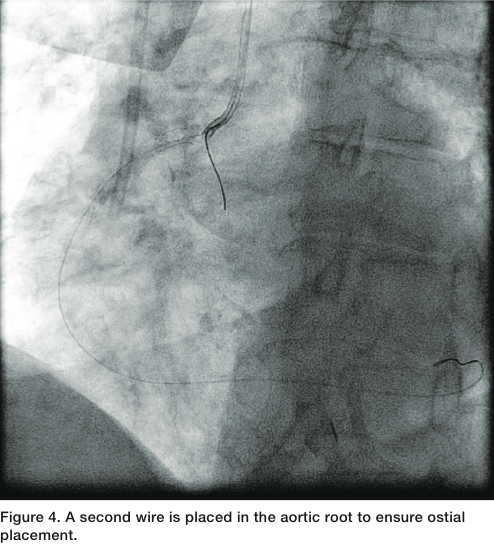

using the Szabo technique1 (Figures 2-3), with a second wire placed in the aortic root to ensure ostial placement (Figure 4). The stent was then advanced to the ostium, deployed, and then the second wire was removed from the proximal strut, ensuring that we were ostial in placement. We post-dilated with a 3.75mm Quantum balloon (Boston Scientific) at high pressure. Final angiography revealed TIMI-3 flow without any dissection, perforation, or embolization. The patient tolerated the procedure well.

The technique was first described by Szabo et al in 2005 and involves a second guide wire placed in the aorta (or branch vessel for a non aorto-ostial lesion) to anchor the stent.1 The stent is prepared by a low pressure inflation (1-2 atm) with the protective sleeve left in place while exposing the proximal struts. The remainder of the stent is compressed with the sleeve. The wire is passed through the proximal strut of the stent followed by crimping of the “lifted” strut; however, not to the degree that the anchor wire is not mobile. The stent then travels over the primary guide wire and the anchor wire, which stops forward motion of the stent at the

vessel ostium (Figures 2-3).3 The stent is then deployed at low or nominal pressure, followed by removal of the anchor wire. The stent balloon can then be reinflated or another balloon can be used to post dilate.